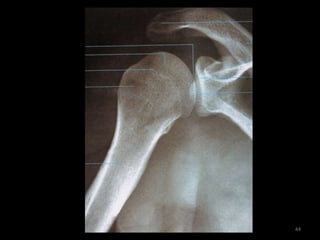

Ombro14

Incidência AP Ombro Rotação Neutra (1)15